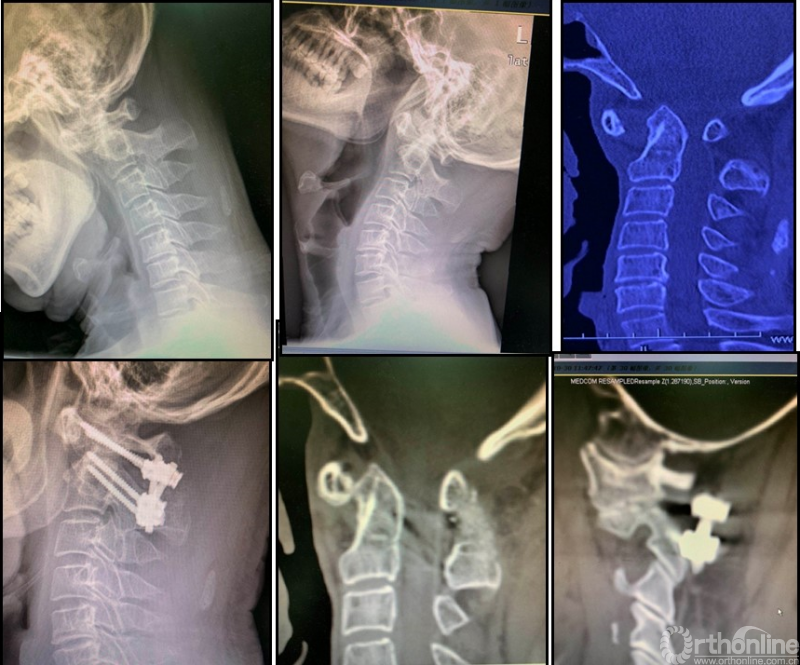

图3:女性56岁;寰枢椎脱位合并寰椎枕骨化畸形、脊髓病。经过动力位X片及术中麻醉后牵引试验,诊断为“难复性寰枢椎脱位”(Type III)。行经口寰枢松解+后路C2椎弓根固定、枕颈固定融合术。寰枢椎脱位获得解剖复位、脊髓压迫解除。

图4 男性55岁、诊断难复性寰枢椎脱位;经过单纯后路手术(侧块关节松解+植骨+钉棒复位固定术)获寰枢椎复位、融合。术后CT显示寰枢椎解剖复位、侧块关节间骨性融合。